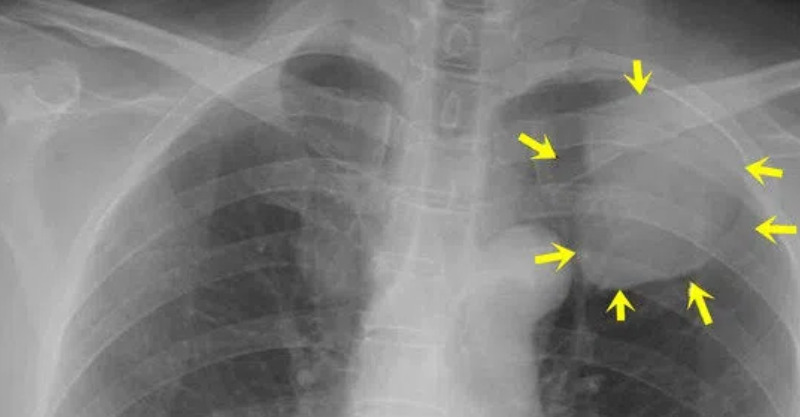

根據《ETtoday》報導,紐澤西紐瓦克市一名急診科醫師2日在《Cureus醫學科學雜誌》分享一個案,透露一名76歲的婦人因為肩膀疼痛難以忍受,緊急掛急診室看診,醫生替她安排精密檢查,做完電腦斷層掃描與骨頭的活體組織檢查後,發現左肺底部有腺癌,竟是肺癌纏身,儘管癌細胞沒有擴散至肩膀,但其中一癌變位置在脊椎上,醫生推測是此處引起肩痛!